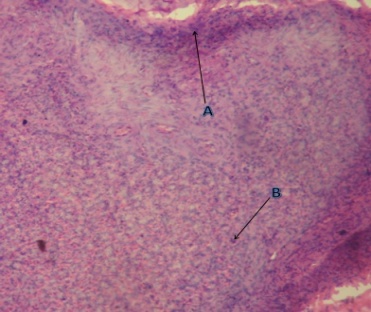

Histological observation of APL and HE stomach ulcer tissues pretreated only with dH2O (control group) showed marked lesions and severe damage to the gastric mucosa, hemorrhagic erosion, edema and leucocytes infiltration in the submucosal layer. On the other hand, stomach tissues of APL and HE ulcers in rats pretreated with 50 mg/kg of F4 sub-fraction showed mild lesions of the mucosa with mild leucocytic infiltration. The tissues after pretreatment with 100 mg/kg of F4 sub-fraction exhibited almost normal mucosal architecture with very few inflammatory cells (fig. 4 and 5). For comparison purposes, stomachs of omeprazole and ranitidine pretreated rats showed moderate protection of the mucosa with very mild hemorrhage and leucocytic infiltration.

Fig. 4: Histopathological evaluation of antiulcer activity of F4 against APL ulcer in rats (HandE stain, 10x magnification). [a] Stomach of the control animal showing severe mucosal erosion and large number of inflammatory cells; [b] Stomach of the 30 mg/kg omeprazole treated animal showing mild mucosal erosion and lesser number of inflammatory cells; [c] Stomach of F4-50 mg/kg treated animal showing mild mucosal erosion and lesser number of inflammatory cells; [d] Stomach of F4-100 mg/kg treated animal showing almost normal mucosa and very few inflammatory cells

F4-chloroform: methanol (7:3) solvent system fraction (most active sub-fraction); A-Mucosal erosion; B-Inflammatory cells